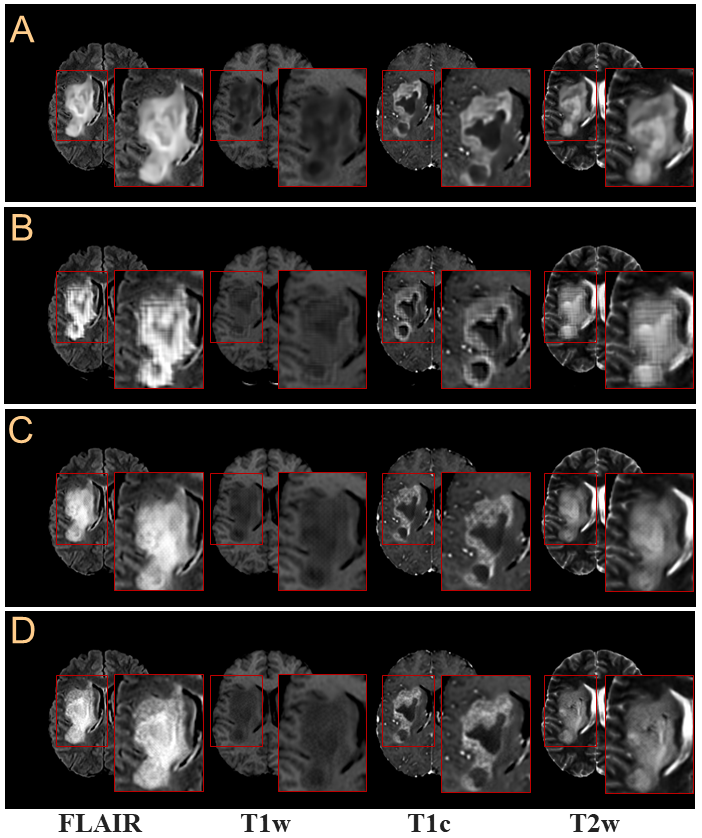

Refer to caption

Figure 7: Synthesized brain tumor images from the proposed network, Ginpaintsubscript𝐺𝑖𝑛𝑝𝑎𝑖𝑛𝑡G_{inpaint}, trained by using various loss functions. The results according to (A) inpaint:pixelsubscript:𝑖𝑛𝑝𝑎𝑖𝑛𝑡𝑝𝑖𝑥𝑒𝑙\mathcal{L}_{inpaint:pixel}, (B) inpaint:pixel+inpaint:advsubscript:𝑖𝑛𝑝𝑎𝑖𝑛𝑡𝑝𝑖𝑥𝑒𝑙subscript:𝑖𝑛𝑝𝑎𝑖𝑛𝑡𝑎𝑑𝑣\mathcal{L}_{inpaint:pixel}+\mathcal{L}_{inpaint:adv}, (C) inpaint:pixel+inpaint:contsubscript:𝑖𝑛𝑝𝑎𝑖𝑛𝑡𝑝𝑖𝑥𝑒𝑙subscript:𝑖𝑛𝑝𝑎𝑖𝑛𝑡𝑐𝑜𝑛𝑡\mathcal{L}_{inpaint:pixel}+\mathcal{L}_{inpaint:cont}, and (D)inpaint:pixel+inpaint:adv+inpaint:contsubscript:𝑖𝑛𝑝𝑎𝑖𝑛𝑡𝑝𝑖𝑥𝑒𝑙subscript:𝑖𝑛𝑝𝑎𝑖𝑛𝑡𝑎𝑑𝑣subscript:𝑖𝑛𝑝𝑎𝑖𝑛𝑡𝑐𝑜𝑛𝑡\mathcal{L}_{inpaint:pixel}+\mathcal{L}_{inpaint:adv}+\mathcal{L}_{inpaint:cont}. Tumor regions in red boxes were enlarged for clear comparison.

The pixel loss function, inpaint:pixsubscript:𝑖𝑛𝑝𝑎𝑖𝑛𝑡𝑝𝑖𝑥\mathcal{L}_{inpaint:pix}, is the simplest and most commonly used loss function in general deep learning algorithms. However, as shown in Fig.7(A), the results tend to be blurry and less realistic. To overcome this problem, we include adversarial loss function, inpaint:advsubscript:𝑖𝑛𝑝𝑎𝑖𝑛𝑡𝑎𝑑𝑣\mathcal{L}_{inpaint:adv}, and content loss function, inpaint:contsubscript:𝑖𝑛𝑝𝑎𝑖𝑛𝑡𝑐𝑜𝑛𝑡\mathcal{L}_{inpaint:cont}, as shown in Fig.7(B)-(D). When inpaint:advsubscript:𝑖𝑛𝑝𝑎𝑖𝑛𝑡𝑎𝑑𝑣\mathcal{L}_{inpaint:adv} is used together with inpaint:pixsubscript:𝑖𝑛𝑝𝑎𝑖𝑛𝑡𝑝𝑖𝑥\mathcal{L}_{inpaint:pix} as shown in Fig.7(B), a lot of lattice artifacts appear. In general, it is due to the instability of learning of the GAN-based algorithm. Here inpaint:contsubscript:𝑖𝑛𝑝𝑎𝑖𝑛𝑡𝑐𝑜𝑛𝑡\mathcal{L}_{inpaint:cont} is used together with inpaint:pixsubscript:𝑖𝑛𝑝𝑎𝑖𝑛𝑡𝑝𝑖𝑥\mathcal{L}_{inpaint:pix} to make the synthesized images look more perceptually realistic as shown in Fig.7(C). Finally, the results of the trained network using all the loss functions are shown in Fig.7(D), where blurring and lattice artifacts are not seen.